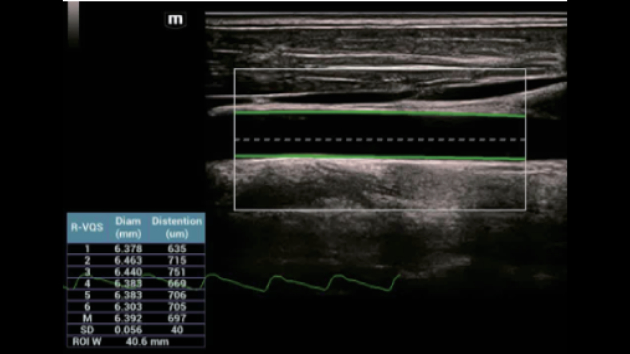

De Consona biedt nieuwe en concrete oplossingen die effici?nt helpen bij het stellen van een vlotte diagnose voor veel verschillende soorten pati?nten.

Ongeacht of u werkzaam bent in een ziekenhuis of kliniek, of uw vaardigheden aanscherpt op het gebied van algemene beeldvormingstoepassingen, vrouwengeneeskunde of cardiovasculaire specialismen, in deze serie vindt u zeer krachtige hulpmiddelen waarmee u aan kop kunt blijven.

Uitgebreide?oplossingen voor beeldvorming aangestuurd door ZST?+

Het ZST+?platform is een buitengewone innovatie en revolutie in de wereld van echografie. Het transformeert echografiegegevens van conventionele bundelvorming naar kanaalgegevensverwerking. Het overwint de traditionele afweging tussen ruimtelijke resolutie, temporele resolutie en weefseluniformiteit, en levert een uitzonderlijke beeldkwaliteit voor oneindige beeldvormingsoplossingen met non-stop verbeteringen.